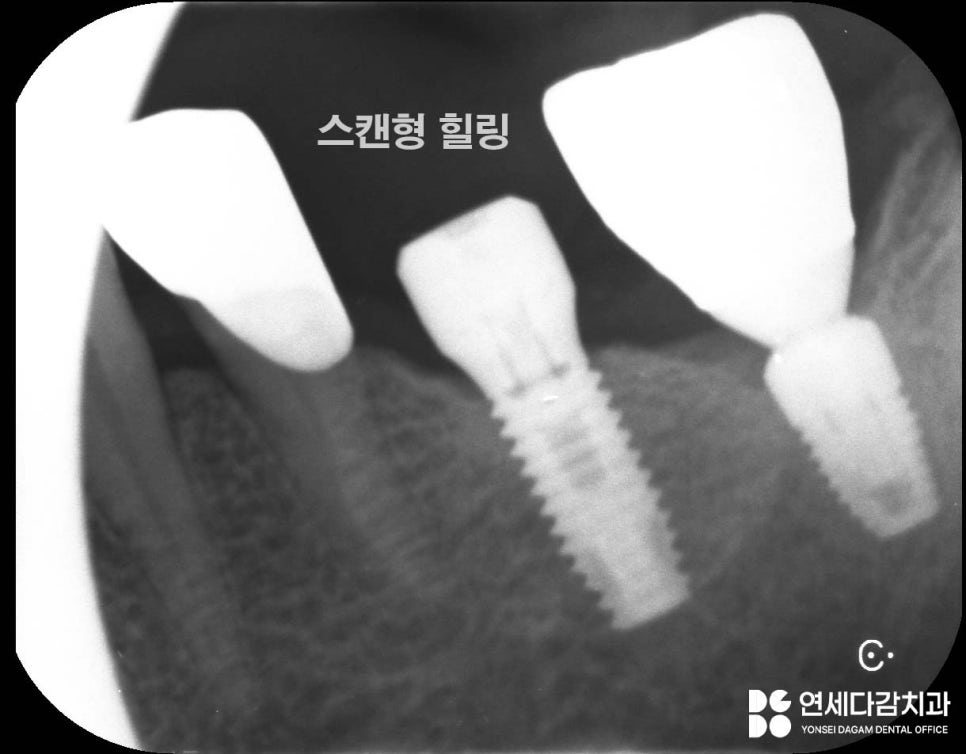

그러나 임플란트의 종류나 모양에 따라

본을 뜨기 위해 필요한

파츠(스캔형 힐링 어벗트먼트)가

필요합니다.

모두 다르게 생겼으나

개롱역 치과 에서는

모든 임플란트 종류의 본을 뜰 수 있도록

파츠를 다 구비하고 있습니다.

맞는 힐링 어벗트먼트를 체결하고 스캔해서

보철물을 재제작이 완료됩니다.